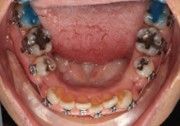

The IOS Mini Cinch Back Plier demonstrated superior control and a significantly reduced risk of bracket debonding and wire deformation compared to the regular Hammerhead plier from a different brand. Wire bends achieved with the IOS Mini Cinch Back Plier maintained integrity even under high-torque activation. The following images illustrate key differences in bend quality, wire distortion, and proximity to the bracket between the IOS Mini Cinch Back Plier and the conventional Hammerhead plier.

The right side shows a full C-bend from cinching too far from the bracket, then re-bending with a regular Hammerhead plier from a different brand.

The right side shows the distortion produced while bending with a regular Hammerhead plier from a different brand.

The right side has an acute (distorted) bend after bending the wire with a regular Hammerhead plier from a different brand.